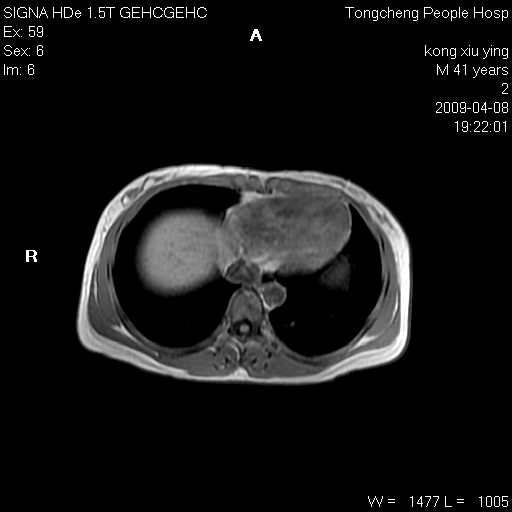

标题: CL1008:【经典】胆囊石榴籽样结石。

女,41岁。健康体检——彩超提示:胆囊显示不清。平素健康,无不适感。

腹部mr扫描及mrcp,图像如下: